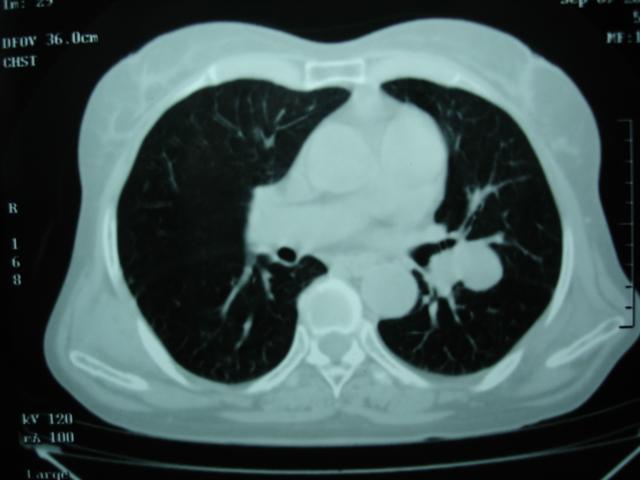

以下是引用卜一在2009-9-7 19:51:00的发言:[br][br] 1 左侧胸内甲状腺占位-多考虑甲状腺腺瘤! 2、左肺门占位-建议增强扫描以便明确性质。 3 慢支并感染! [br]

以下是引用shibing在2009-9-7 20:40:00的发言:[br]左侧胸内甲状腺占位-多考虑甲状腺腺瘤! 2、左肺门占位-建议增强扫描以便明确性质。 3 慢支并感染! [br]